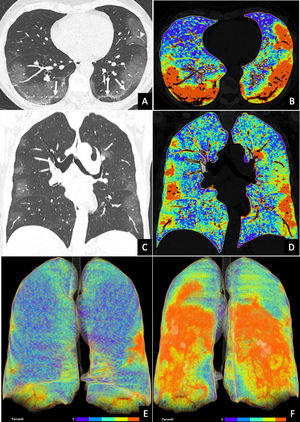

Mujer de 57 años con sintomatología progresiva de febrícula, disnea y tos escasamente productiva de una semana de evolución. La radiografía de tórax mostró un aumento de densidad mal definido en campo medio izquierdo sugestivo de infección atípica. La reacción en cadena de la polimerasa (PCR) fue compatible con infección por SARS-CoV-2. Las imágenes de tomografía computarizada (fig. 1) en los planos axial (fig. 1A) y coronal (fig. 1B) mostraron una afectación multilobar, bilateral con patrón predominante en vidrio deslustrado de distribución periférica y predominio posterior, líneas subpleurales e ingurgitación vascular. Fue diagnosticada de enfermedad por coronavirus (COVID-19)1,2. Las imágenes se posprocesaron con un programa comercial (Pulmo3D, syngo®.via, Siemens Healthineers), que codifica en color los percentiles de valores de atenuación, permitiendo conocer la extensión y cuantificar la carga inflamatoria (figs. 1C y D). Las reconstrucciones volumétricas también demostraron la extensión total de la afectación inflamatoria y su localización, respetado los segmentos anteriores (E) y englobando fundamentalmente los segmentos posteriores (F). Este tipo de posprocesamiento 3D permite establecer la presencia, localización y extensión de la afectación pulmonar y cuantificar la carga inflamatoria. Su utilidad clínica y valor pronóstico en COVID-19 deberán ser evaluados en estudios posteriores.

A y B) Imágenes de la tomografía computarizada, el plano axial (A) y el plano coronal (B). C y D) Posprocesamiento de las mismas imágenes en percentiles de valores de atenuación. E y F) Reconstrucciones volumétricas en las proyecciones anterior (E) y posterior (F). Las imágenes de la tomografía computarizada muestran un patrón predominante en vidrio deslustrado de distribución periférica y predominio posterior con líneas subpleurales (flechas) e ingurgitación vascular (punta de flecha), signos compatibles con COVID-19. Nótese que la codificación en color de los percentiles de valores de atenuación permite cuantificar la extensión de la inflamación y la carga inflamatoria. La extensión de la inflamación, afectando fundamentalmente a los segmentos posteriores, se pone de manifiesto de manera más visual en las reconstrucciones volumétricas (en color azul se muestra la densidad pulmonar normal, mientras que los colores anaranjados y rojos muestran la actividad inflamatoria).